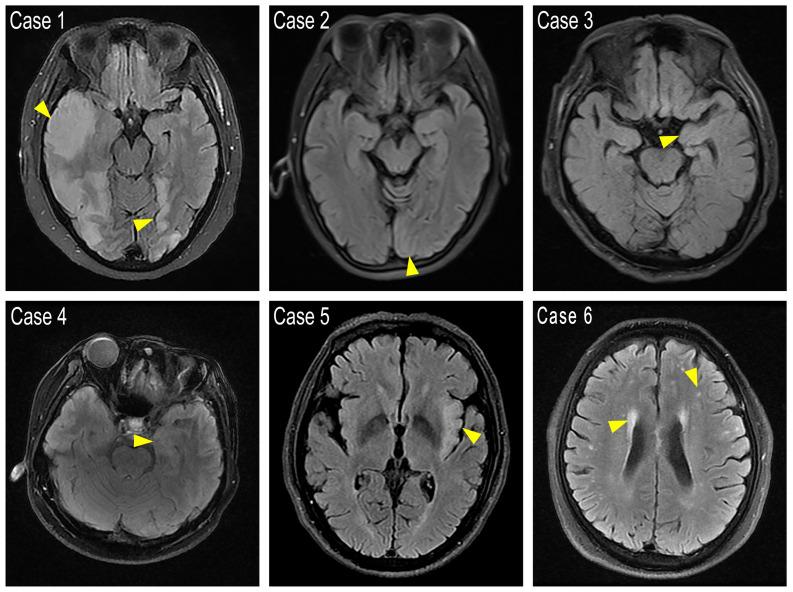

Twenty-six patients, 10 females (38.5%) and 16 males (61.5%), diagnosed with anti-GABABR encephalitis were studied. The median age was 58 years. Of the 23 cases with complete clinical data, their main manifestations were epileptic seizures (65%), mental and behavioral abnormalities (52%), and cognitive impairment (48%). 7 (30.4%) cases had tumors: 5 small cell lung cancer (SCLC), 1 rectum adenocarcinoma (moderately differentiated) and 1 esophageal squamous cell carcinoma. MRI showed 5 (22%) cases had T2 FLAIR increased signals in cortex but with different regions affected. One of the two patients scanned for PET-CT showed hypermetabolism in the left temporal lobe region. The disease course ranged from 5 days to 3 years. 2 patients (one had esophageal carcinoma) without immunotherapy and 3 patients (one had SCLC) that did not response to immunotherapy died soon after diagnosis. 18 patients improved after immunotherapy while 3 (all had SCLC) died after relapses. The prevalence of epileptic seizures and malignancies was significantly lower in the survival group than in the deceased group at 18-months follow-up, the same as the admission mRs score. Serum fibrinogen, cerebrospinal fluid immunoglobulin G quotient, and 24-hour intrathecal synthesis rate were significantly lower in the survival groups as well.

Cortex T2 FLAIR abnormalities were only observed in a small proportion of anti-GABABR encephalitis patients with heterogeneous MRI phenotypes. High mRS score at admission, epileptic seizures and the presence of a tumor indicated a poor prognosis, while the underlying mechanism of the later two factors should be investigated further.